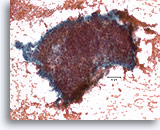

Papilloom, Borst FNA, Celblok.

Immunokleuring met p63 van de coupes van de patiënt in afbeelding 23-25 helpt de myoepitheliale cellen te markeren die door deze papilloom verstrooid zijn.

10X

Papilloom, Borst FNA, Celblok.

Immunokleuring met p63 van de coupes van de patiënt in afbeelding 23-25 helpt de myoepitheliale cellen te markeren die door deze papilloom verstrooid zijn.

10X